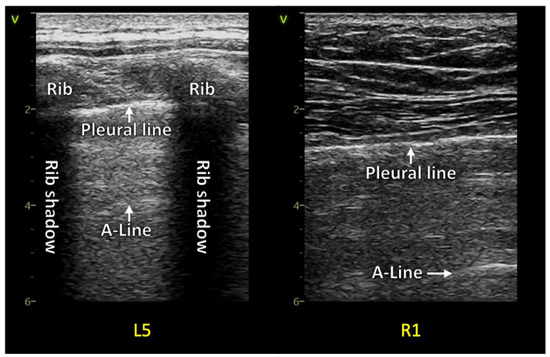

1.1.1. Reverberation Artifacts

1.1. Background Lung Ultrasound